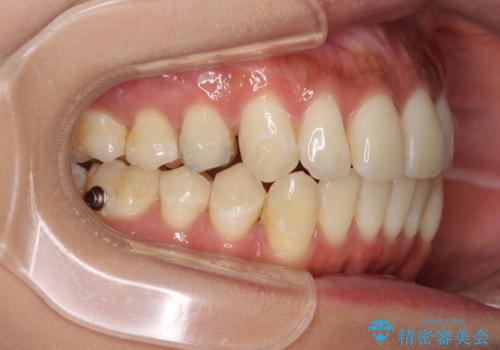

- 学生の頃に矯正治療を行ったものの、保定を怠けてしまったことによる後戻りを気にして来院された患者様です。

根管治療が必要な歯があったため、矯正治療前に根管治療を行い、その後はインビザラインにより矯正治療を行うこととしました。

下顎の八重歯が上顎歯列に収まる過程で咬みにくさがありましたが、最終的には、咬み合わせも安定し、きれいに歯列を整えることができました。